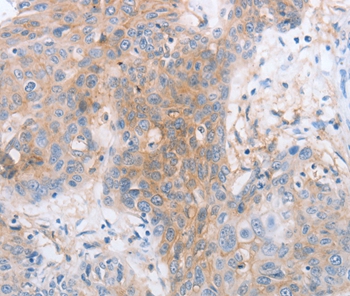

分类: 科研抗体货号: P42772别名: ILT4; LIR2; CD85D; LIR-2; MIR10; LILRA6; MIR-10应用: IHC反应种属: Human